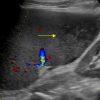

Nhồi máu lách

» Thông tin: Nam giới – 74 tuổi.

» Lâm sàng: Đau mạn sườn trái.